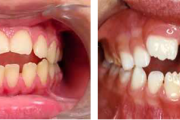

Normaalse jäävhammaskonna pilt küljelt ja eest vaadatuna.